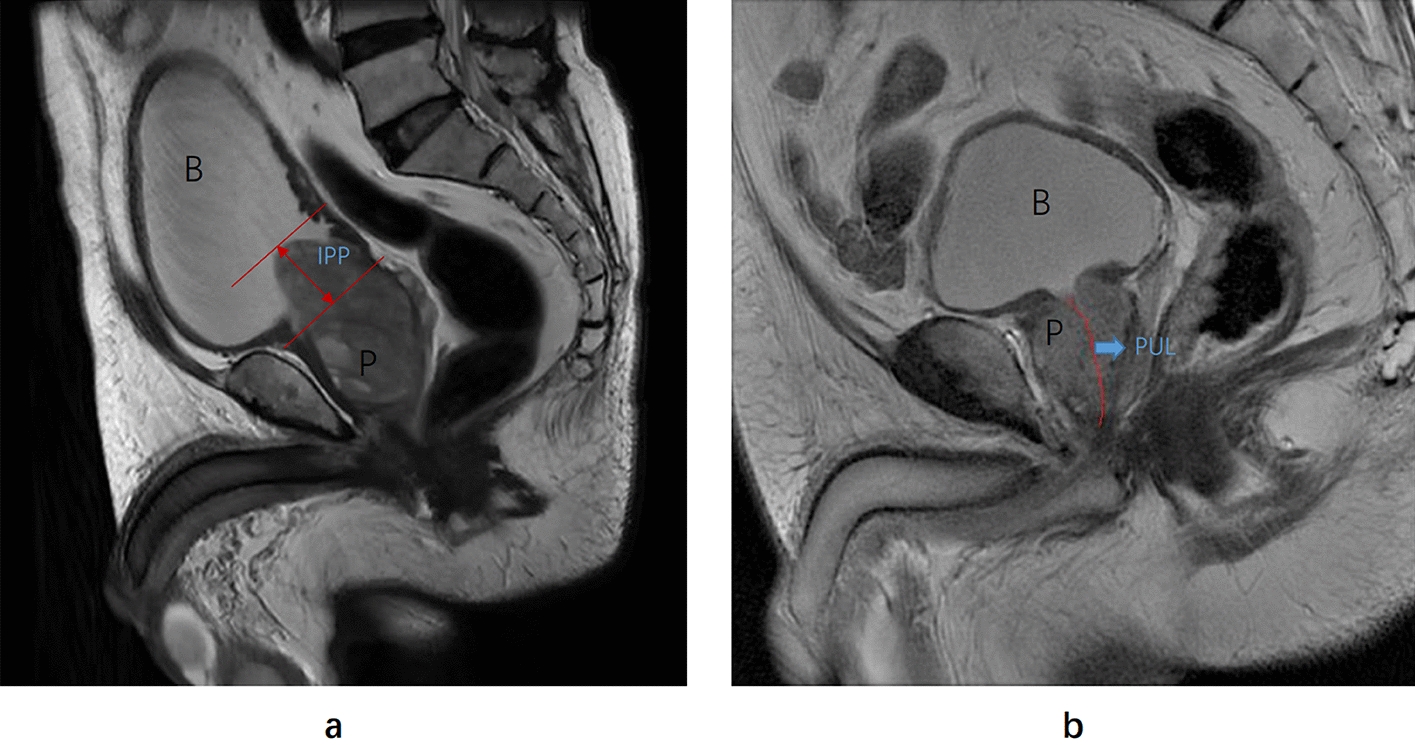

PCAR refers to the ratio of the maximum transverse area of the prostate to the area of a hypothetical circle with the same circumference [1214]. In this study, we selected the T2-weighted transverse section of the prostate with the maximum cross-sectional area, and calculated its area (S) and circumference (L) using the Open Source Computer Vision Library in Python. The area of the hypothetical circle with the same circumference was calculated as S' = L2/4π. Therefore, according to the definition of PCAR, PCAR = 4πS/L2. PV represents the prostate volume, which we calculated during prostate modeling. IPP is the vertical length from the protrusion of the prostate to the base of the bladder, first described by Chia [22], and can be measured using sagittal plane MRI [23]. PUL is the length from the base of the prostate to the apex of the prostate in midsagittal plane MRI [24]. Based on the methodology described above, we utilized T2-weighted sagittal images to measure the IPP and PUL, as illustrated in Fig. 2. It’s important to note that these prostatic anatomical parameters were measured based on MRI rather than ultrasound imaging. All researchers responsible for measuring or calculating these parameters were blinded to other clinical data.

Fig. 2

The measurement of the intravesical prostatic protrusion (IPP) and prostatic urethral length (PUL) on T2-weighted sagittal magnetic resonance imaging: a IPP is the vertical length from the protrusion of the prostate (P) to the base of the bladder B. The red line represents the IPP measurement. This patient is 72 years old with an IPP of 25.3 mm. b PUL is the length from the base of the prostate (P) to the apex of the prostate in midsagittal on MRI. The red line represents the PUL measurement. This patient is 68 years old with a PUL of 4.5 cm